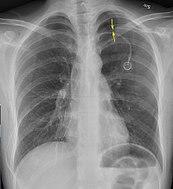

Chest X-ray showing a pneumothorax on the right (left in the image), where the absence of lung markings indicates that there is free air inside the chest

Chest X-ray showing the features of pneumothorax on the left side of the person (right in image)

A plain chest radiograph, ideally with the X-ray beams being projected from the back (posteroanterior, or "PA"), and during maximal inspiration (holding one's breath), is the most appropriate first investigation.[25] It is not believed that routinely taking images during expiration would confer any benefit.[26] Still, they may be useful in the detection of a pneumothorax when clinical suspicion is high but yet an inspiratory radiograph appears normal.[27] Also, if the PA X-ray does not show a pneumothorax but there is a strong suspicion of one, lateral X-rays (with beams projecting from the side) may be performed, but this is not routine practice.[14][18]